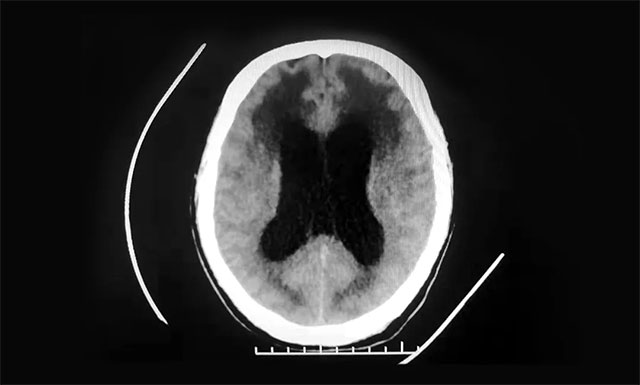

▲ 患者脑室明显扩张,脑脊液已渗入脑组织

医院神经外科6A病区侯增欣主任团队结合患者既往病史,有针对性地对患者开展了系统的检查,余先生的定向力、计算力和记忆力均有所下降,精神状态差,意识障碍较为明显。行CT检查可见,患者脑干体积缩小,脑室系统中度扩张,充盈的脑脊液已部分渗入了脑组织,形成间质性脑水肿,情况比较严重。